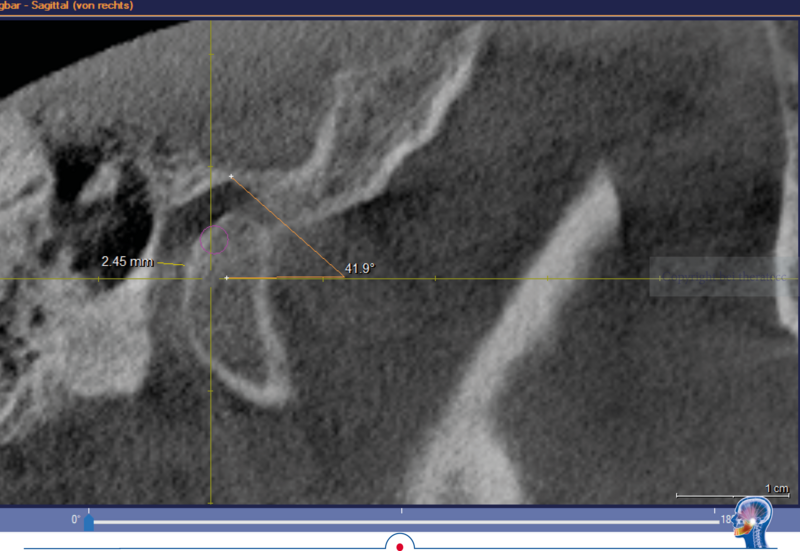

In dem hier vorgestellten Fall wurden diese Parameter zusätzlich im DVT bestimmt. Die im DVT ermittelte sagitale Gelenkbahnneigung beträgt rechts 41,9° und links 38,3°. Die mit Centric Guide® 3D ermittelte Gelenkbahnneigung beträgt rechts 43,86° und links 38,03°. Damit weichen die beiden Werte rechts nur um 1,96° und links nur um 0,27° voneinander ab. Wenn man sich die Gelenkbahneinstellung im Vollwertartikulator anschaut, stellt man schnell fest, dass diese nur in 5° Schritten erfolgt.

Mit der DVT Auswertung konnte nachgewiesen werden, dass die mit Centric Guide® 3D erfassten Parameter exakt mit der Anatomie des Patienten übereinstimmen. Kurz um man kann diesen Parametern definitiv vertrauen.